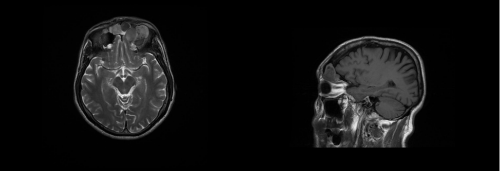

4. Eight months after the symptoms recurred so the patient underwent diagnostic nasal endoscopy that showed a large area of fibrosis at the region of the left frontal-nasal duct. A CT scan showed bilateral recurrence of mucocele within a mega-frontal-sinus. The lesion reached the left supraorbital region with erosion of the roof of the ipsilateral orbit (Figure 1).

Figure 1 CT scan coronal view. The lesion reached the left supraorbital region with erosion of the roof of the ipsilateral orbit.